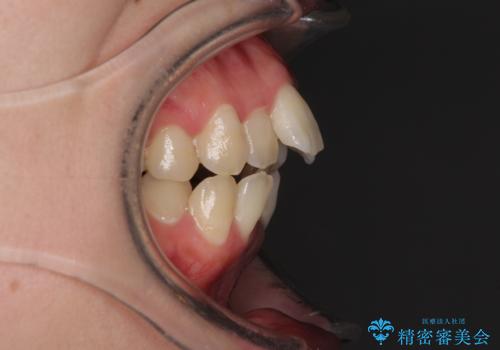

- 口元の突出感を気にして来院された患者様です。

上下左右の第一小臼歯4本を抜歯して口元を下げる治療計画としました。

舌の突出癖が強く、口元を引っ込める力に拮抗してしまい、抜歯スペースを閉じるまでに時間がかかりました。